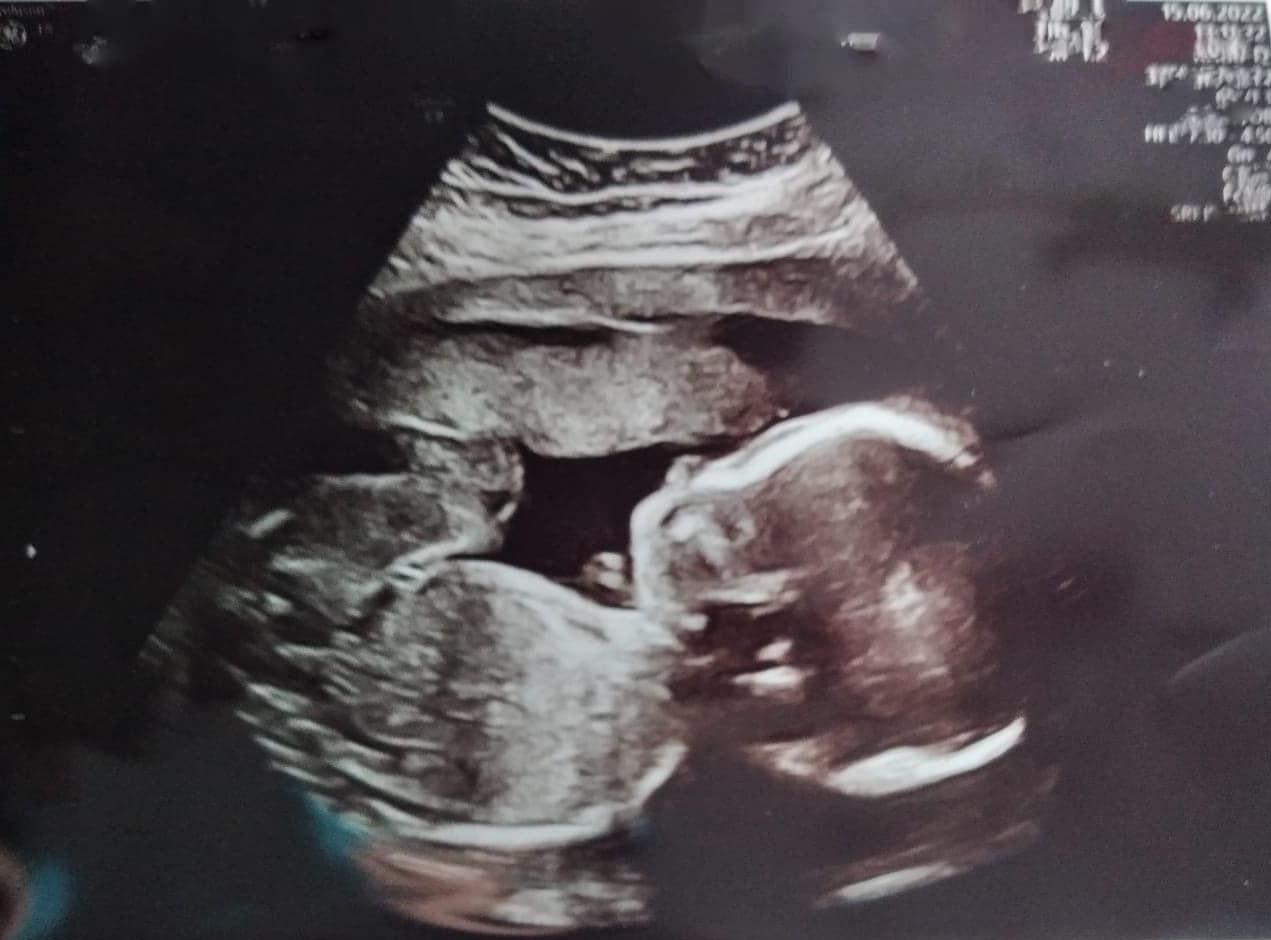

Die Niederösterreicherin Caroline F. erwartet im Oktober ihr erstes Kind (Bild). Nach dem plötzlichen Tod ihres Verlobten muss sie das Baby alleine großziehen.

Niederösterreicherin Caroline F. erwartet im Oktober ihr erstes Kind. Das muss sie nach dem plötzlichen Tod ihres Verlobten nun alleine großziehen.